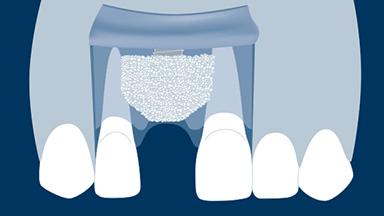

Quando um dente é extraído, o osso alveolar que suporta o dente é reabsorvido ao longo do tempo. Essa reabsorção resulta em uma redução no volume ósseo alveolar, como mostrado neste exemplo clínico de um incisivo central superior direito ausente. O osso diminuiu significativamente na largura orofacial, e isso está em conflito com o requisito fundamental da implantodontia de que os implantes são instalados na posição correta determinada pela prótese dentária. Quando o osso alveolar é reabsorvido, muitas vezes é necessário aumentá-lo para garantir que os implantes possam ser instalados corretamente e completamente incorporados ao osso. Este módulo descreverá uma técnica específica para aumento ósseo conhecida como regeneração óssea guiada ou ROG.